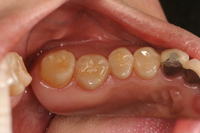

もう1つ症例を見てみましょう。

奥歯2つをコンポジットレジンで修復しました。